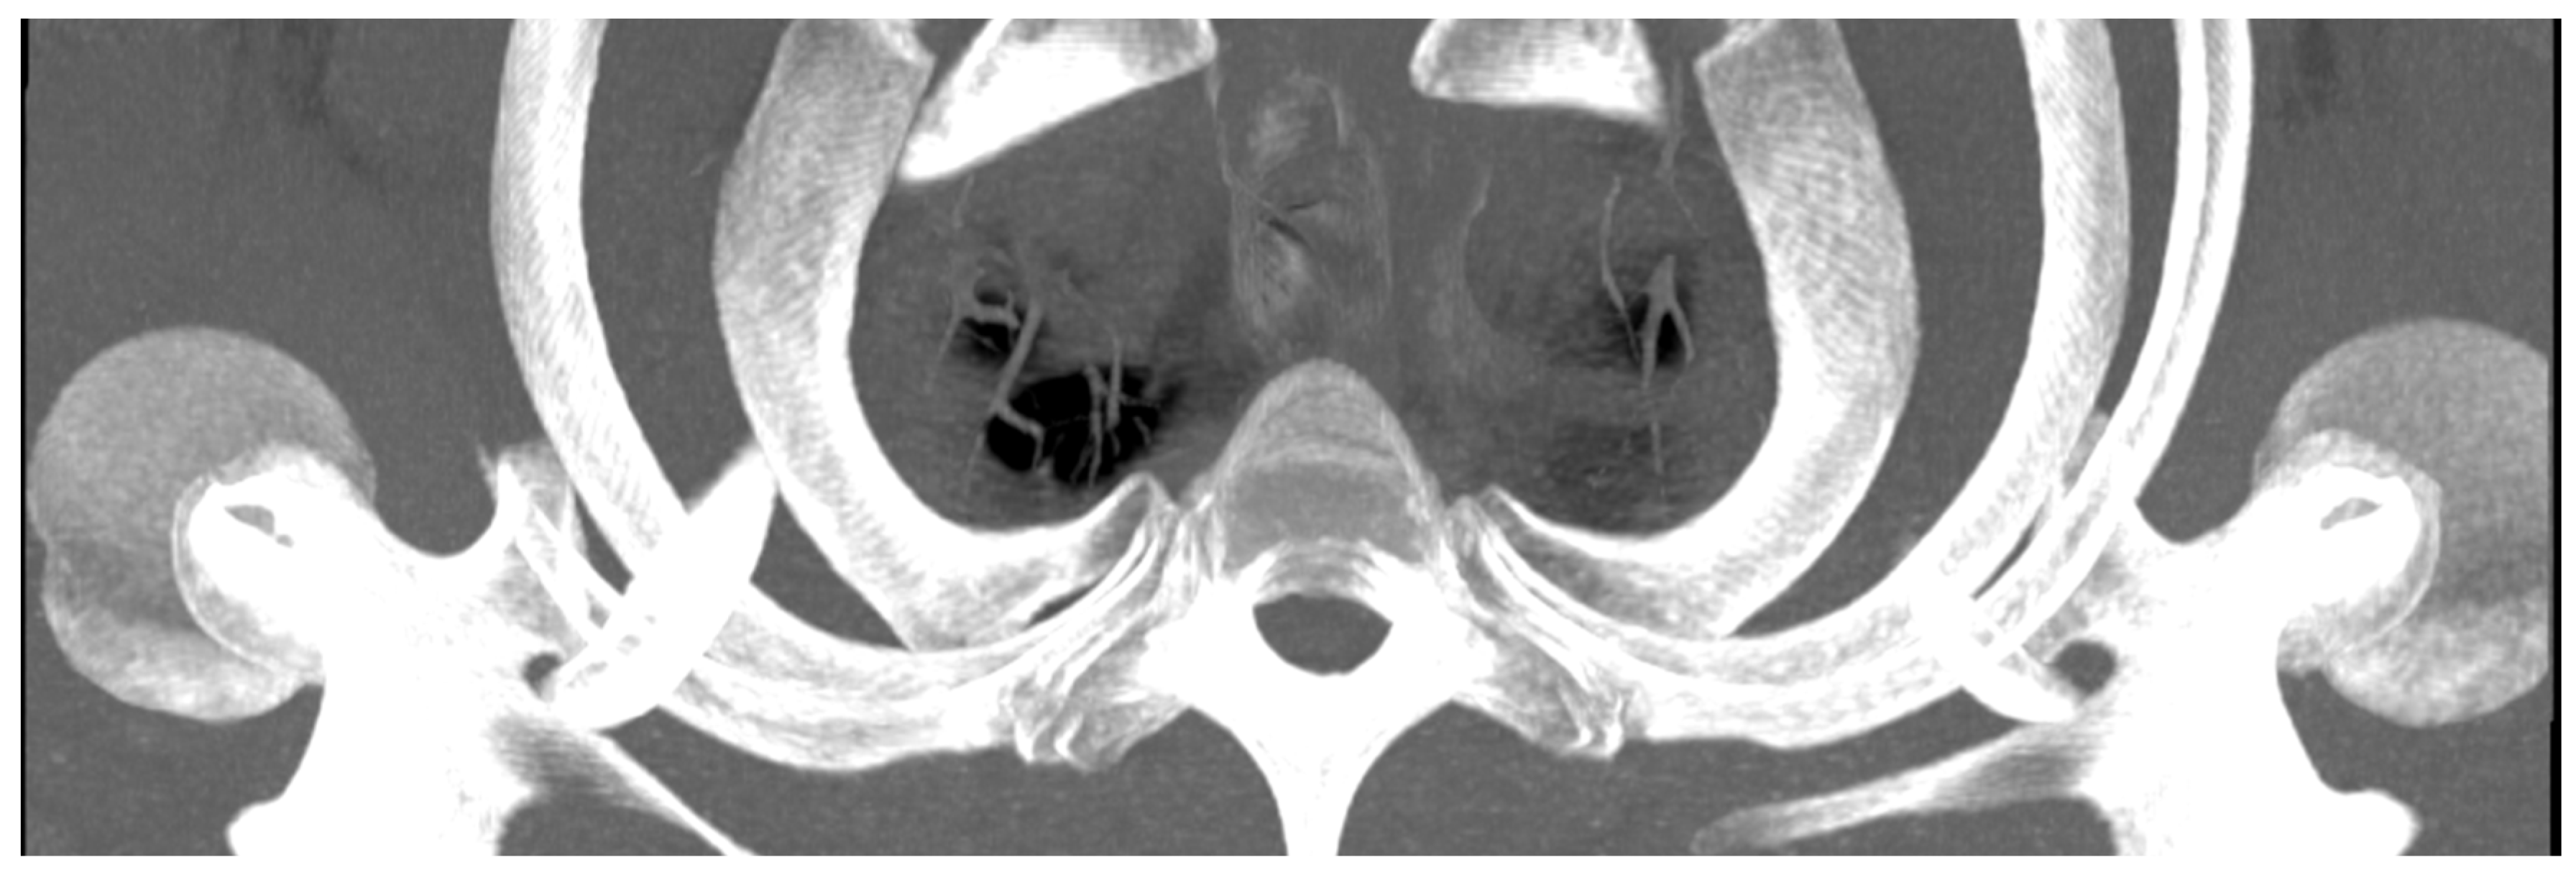

The ‘slab thickness’—the thickness of the layer, shown in mm—was increased step by step, as not all structures of the area to be examined lie in one plane in a cross-section. This was performed so that all areas of interest were included in the image, but not covered by other structures. In this way, individual slices were superimposed on one another. This allows a thick cross-section of a three-dimensional object to be displayed in two dimensions, as shown in Figure 5.

Figure 5.

Example of significantly increased slab thickness showing multiple ribs in a caudocranial view.